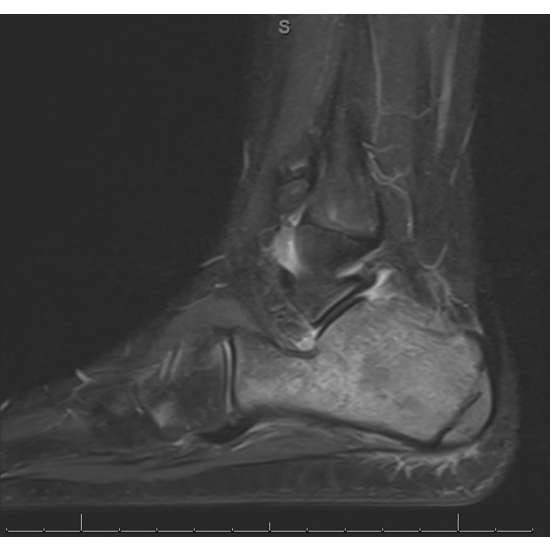

| Not The Average Heel Pain - Page #3 | |||